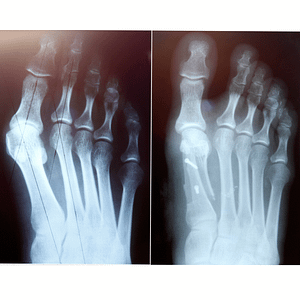

And he did: bunions — on both feet.

A bunion (hallux valgus) is not just a bump on the side of the foot.

It’s a structural misalignment of the big-toe joint:

- The long bone behind the big toe shifts outward

- The big toe angles inward

- The joint becomes more prominent, irritated and sensitive

How Bunions Are Classified

Doctors classify bunions using the Hallux Valgus Angle (HVA), which measures how far the big toe shifts inward.

A mild bunion has an angle of less than 20°, showing only a slight inward tilt.

A moderate bunion measures 20° to 40°, where the bump becomes noticeable and the toe deviates more clearly.

A severe bunion is greater than 40°, creating a strong inward angle where the big toe may start to touch or crowd the second toe.